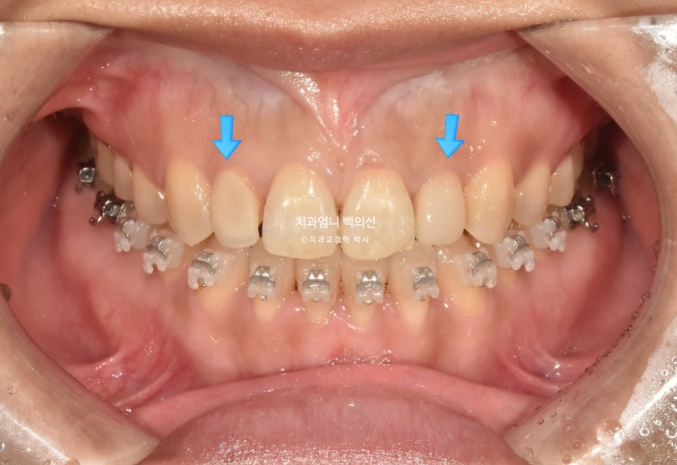

23.10

치료 시작 5개월차, 어금니 함입만으로도 앞니 개방교합이 많이 해소가 되었습니다.

사진에서 보듯이 어금니가 잇몸에 파묻히기 직전까지 함입을 시켰으니 이제 남은 개방교합은 앞니쪽에서 해결을 봐야죠. 이때부터 앞니를 정출시키기 위해 클리피씨 장치를 위아래 모두 부착했습니다.